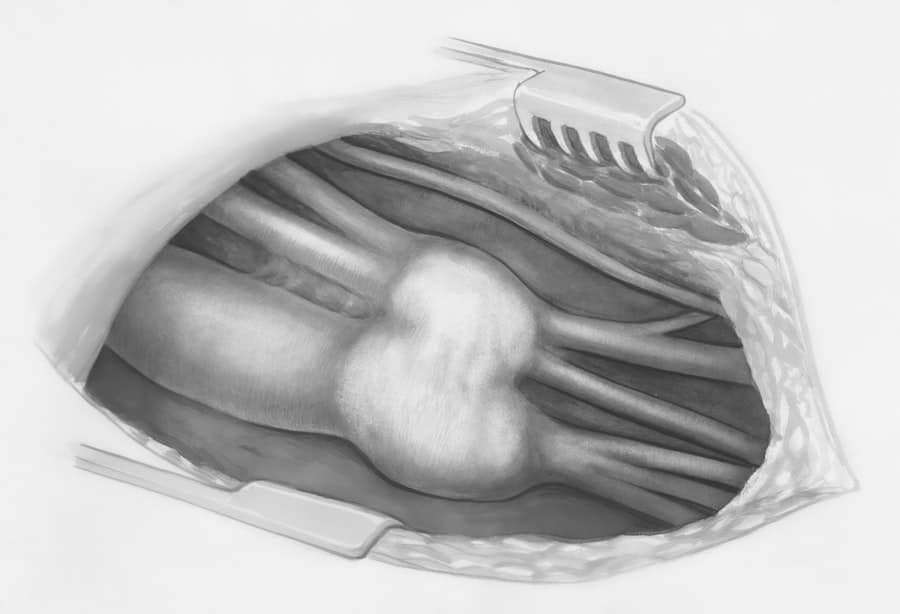

Your nose is a complex structure composed of bone and cartilage, covered by skin and soft tissue. The interplay of these elements dictates its shape, size, and function.

The upper portion of your nose is supported by the nasal bones. These bones contribute to the bridge of the nose and can be a focal point for procedures aimed at reducing or augmenting the dorsal profile.

The lower two-thirds of your nose are primarily composed of cartilage. This includes the septal cartilage, which divides the nasal cavity, and the alar cartilages, which shape the nasal tip and nostrils. The size, shape, and rigidity of these cartilages significantly influence the achievable results of rhinoplasty.

Sculpting and Reshaping the Nasal Structures

The surgeon will meticulously reshape the bone and cartilage to achieve your desired aesthetic and/or functional improvements. This may involve removing excess bone or cartilage, grafting tissue from other areas of your body (such as your ear or rib) to augment or support certain structures, or repositioning existing tissues.